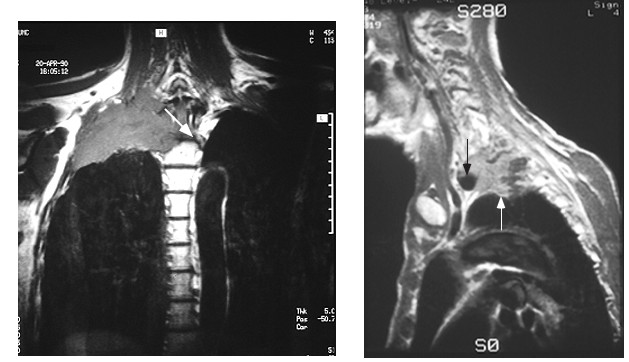

What makes Pancoast tumors unique is that the patient often presents with severe pain and neurologic symptoms but minimal lung symptoms often delaying making the correct diagnosis. CT scans and MRI scans are usually markedly abnormal (go here and here). More CT scans here, here, here

Pancoast Tumor seen on MRI